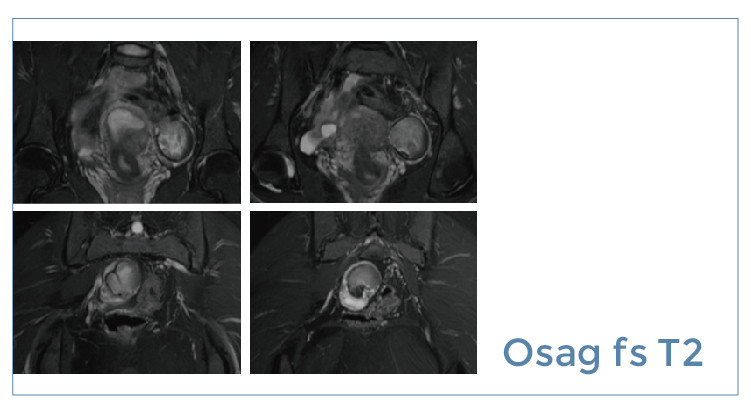

【朗润影像档案】磁共振影像病例分享(编号20190705)